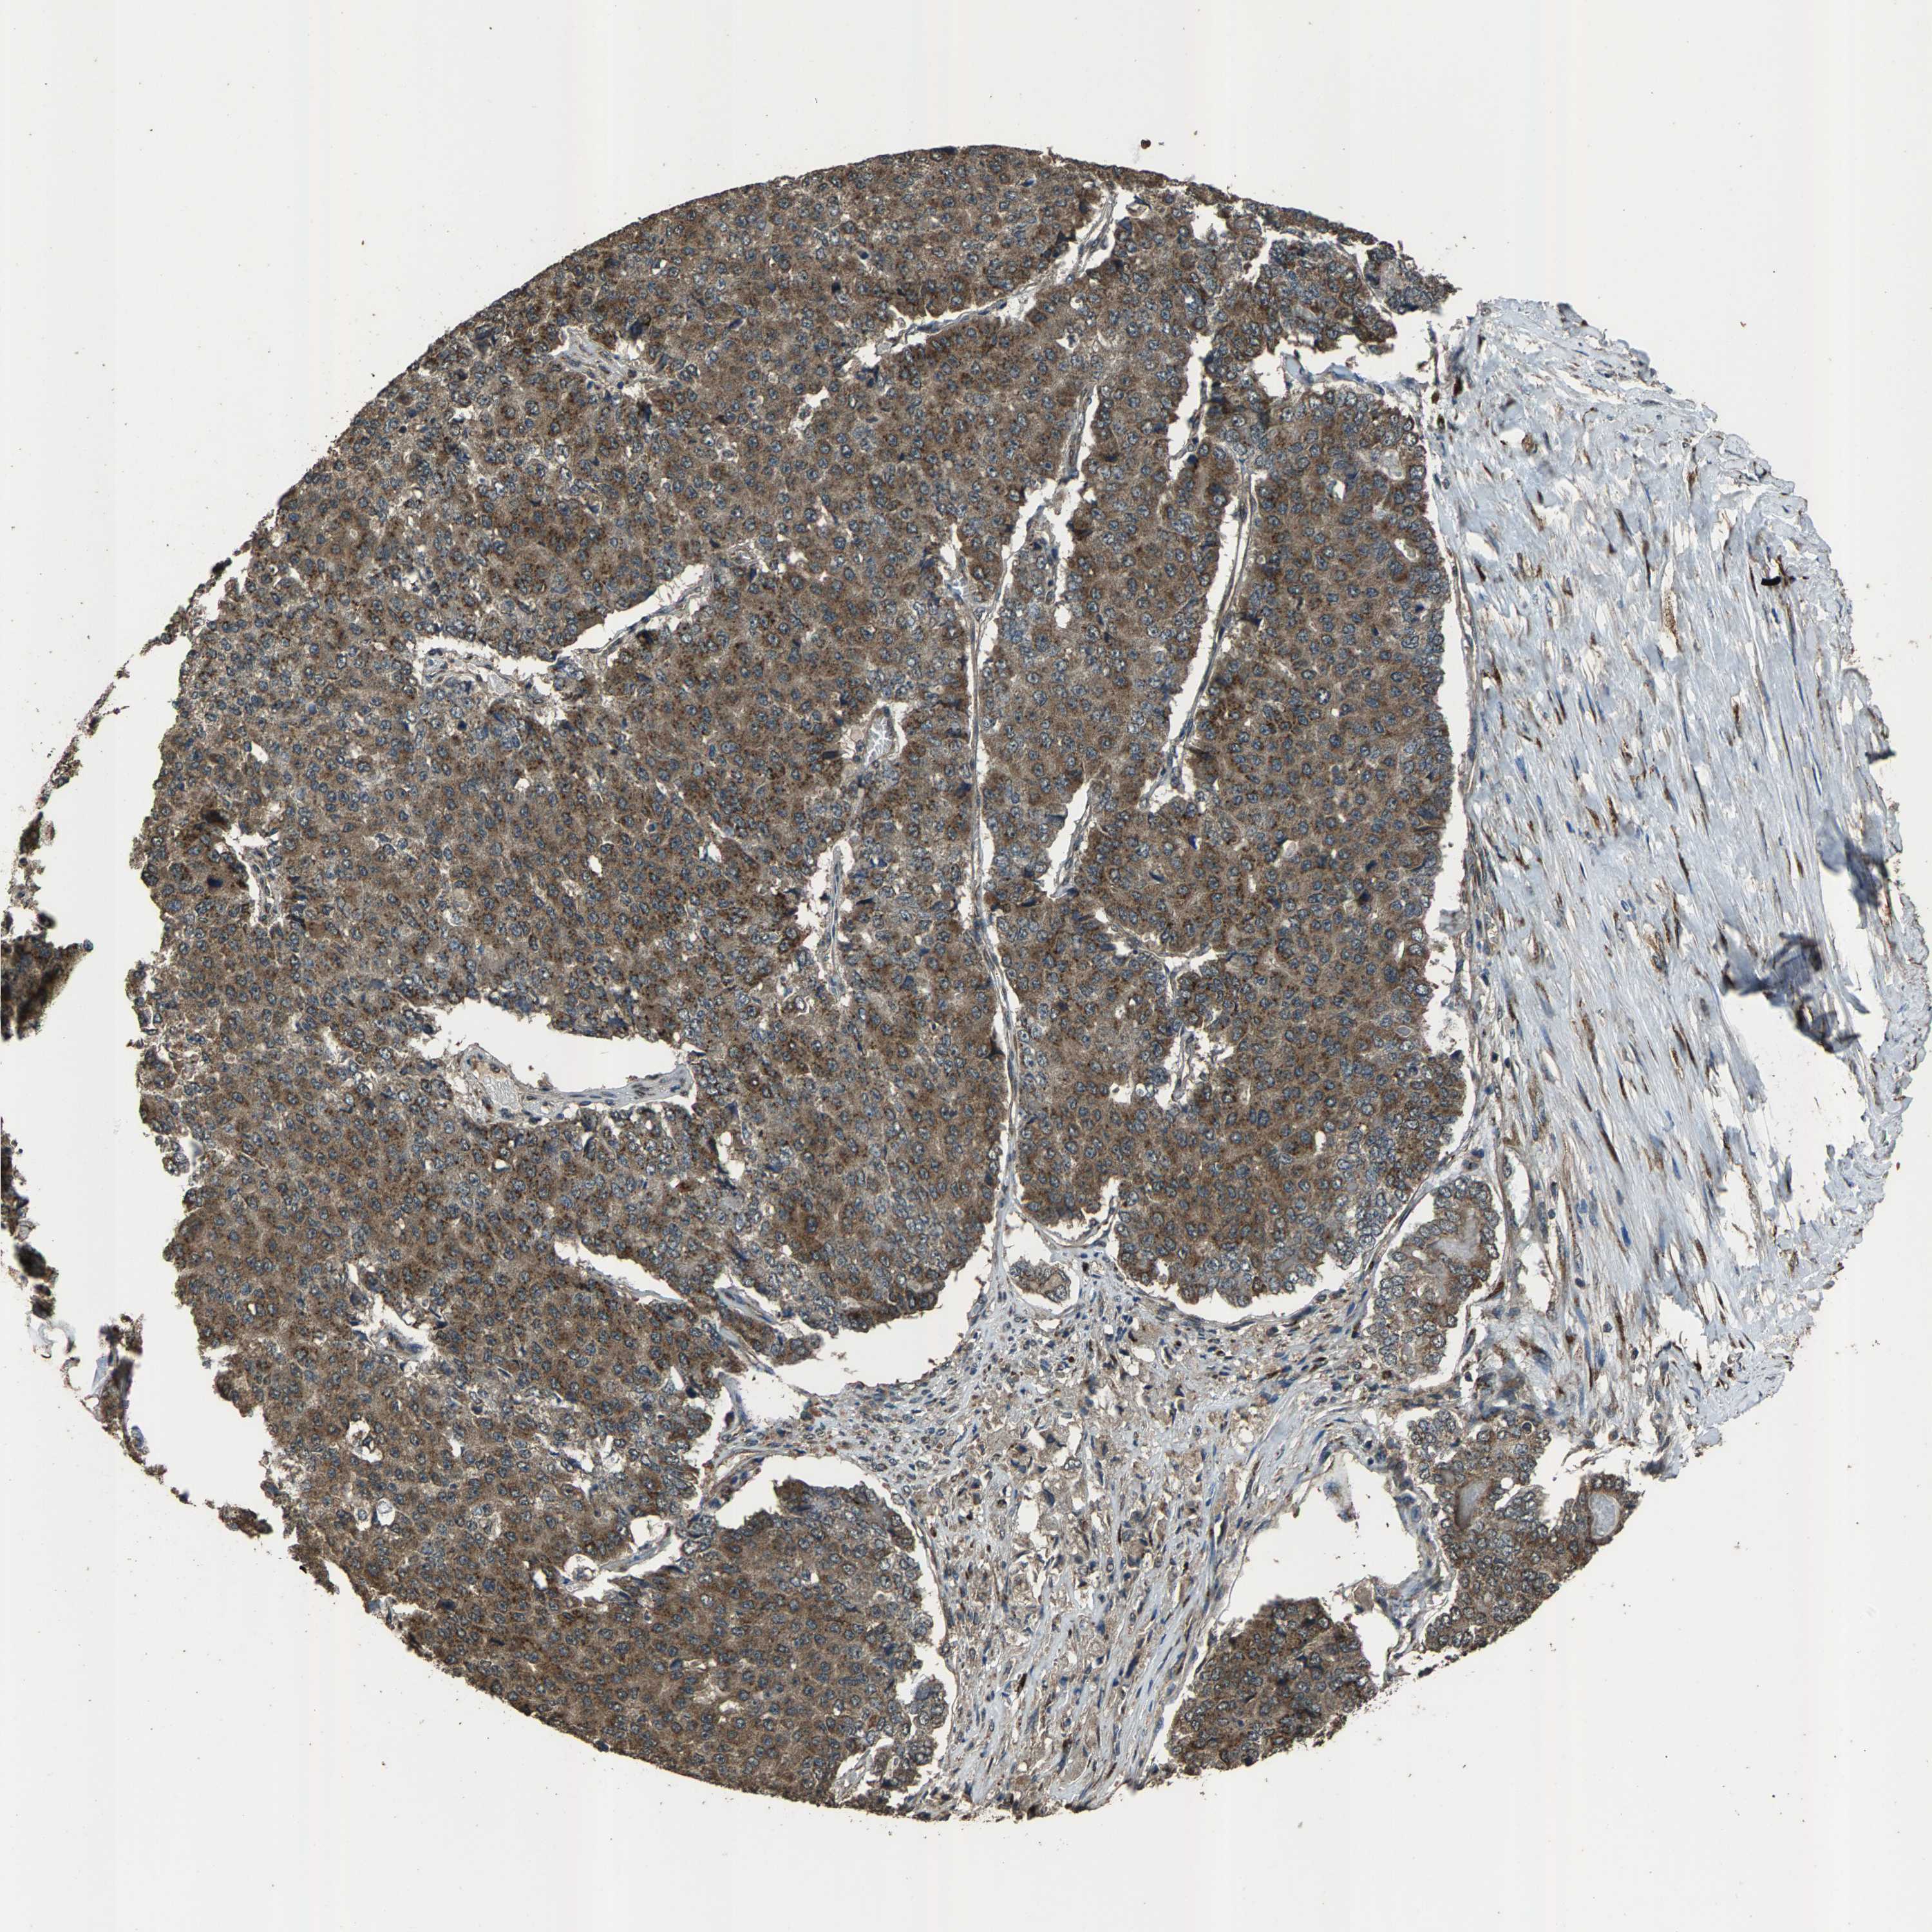

PANCREATIC CANCER - Protein expressioni

A mouse-over function shows sample information and annotation data. Click on an image to view it in a full screen mode. Samples can be filtered based on level of antibody staining by selecting one or several of the following categories: high, medium, low and not detected. The assay and annotation is described here.

Note that samples used for immunohistochemistry by the Human Protein Atlas do not correspond to samples in the TCGA dataset.

Antibody stainingi

Antibody staining in the annotated cell types in the current human tissue is reported as not detected, low, medium, or high, based on conventional immunohistochemistry profiling in selected tissues. This score is based on the combination of the staining intensity and fraction of stained cells.

Each image is clickable and will lead to virtual microscopy that enables deeper exploration of all samples and also displays staining intensity scores, fraction scores and subcellular localization as well as patient and tissue information for each sample.

Antibody HPA021374

Antibody HPA023161

Antibody HPA024631

Staining

High

Medium

Low

Not detected

Intensity

Strong

Moderate

Weak

Negative

Quantity

>75%

75%-25%

<25%

None

Location

Nuclear

Cytoplasmic/membranous

Cytoplasmic/membranous,nuclear

Adenocarcinoma, NOS